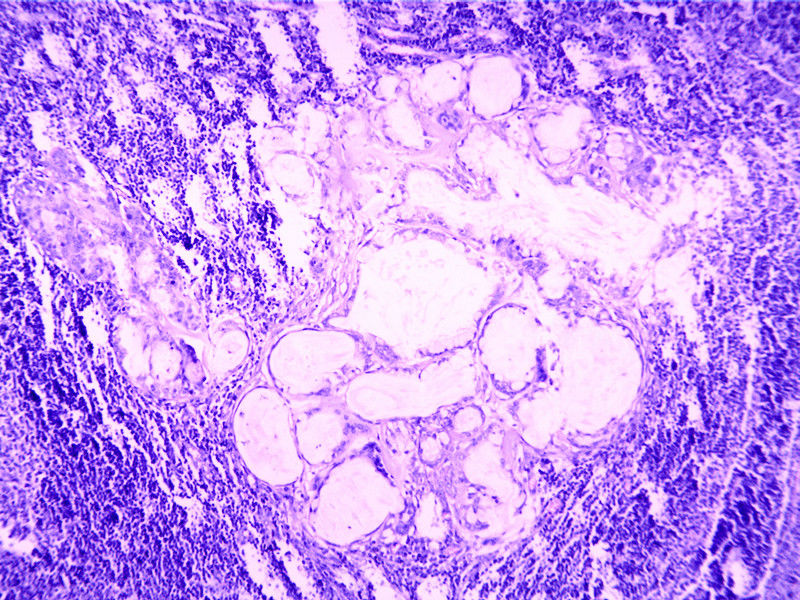

要想Hold住这个肿物的病理诊断,需要了解:

需要鉴别的肿瘤:

(1)皮脂腺淋巴腺瘤

(2)伴有淋巴组织间质的皮脂腺癌(皮脂腺淋巴腺癌)

(3)良性淋巴上皮病

(4)粘膜相关淋巴组织淋巴瘤(MALT淋巴瘤)

(5)转移性粘液表皮样癌